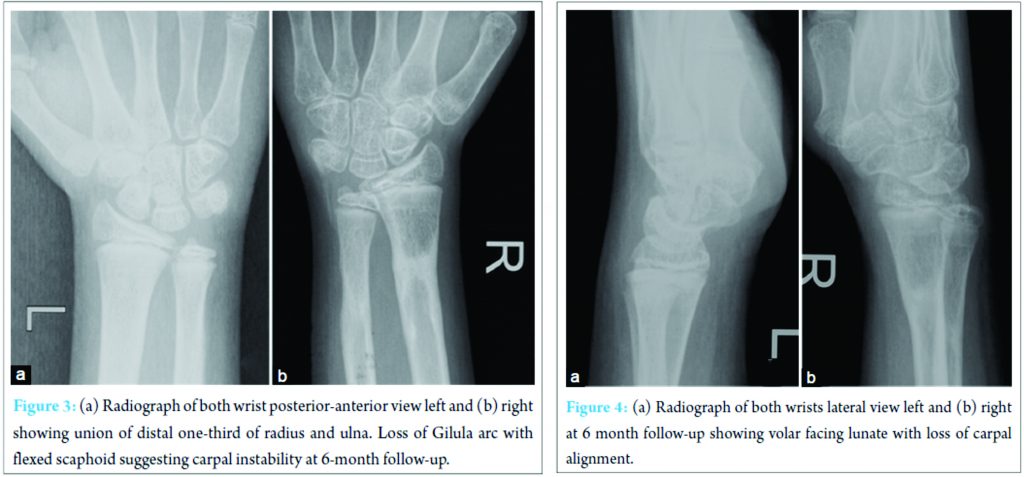

He noticed restriction of dorsiflexion of wrist, while other movements normal. Serial X‑rays showed a loss of normal alignment of radio‑lunate in comparison with the opposite (Fig. 3, 4).

Initial X‑ray showed normal alignment of carpus before reduction. Serial radiographs during follow‑up showed a volar facing lunate with alteration of scapholunate and lunatocapitate angle and was diagnosed with a volar intercalated lunate instability (Fig. 5). The patient was put on strict rehabilitation protocol and the dorsiflexion improved from 0‑10° to 0‑40°. At 1 year follow‑up patient is still having restriction of dorsiflexion (Fig. 6) with volar lunate instability (Fig. 5). The patient is being planned for further procedure.